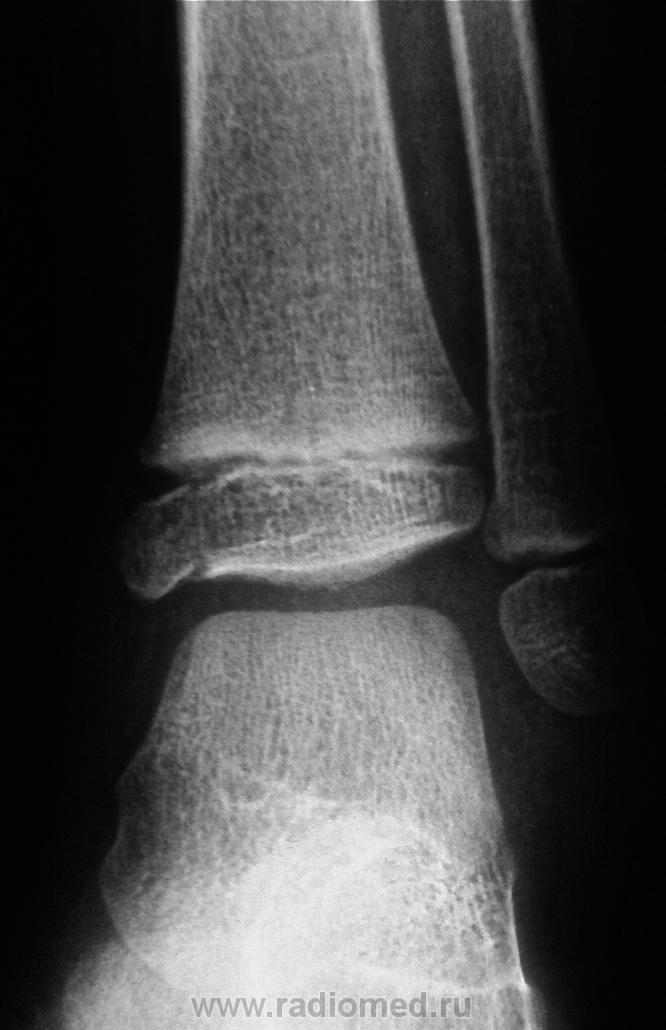

Кроме всего есть еще явный подвывих стопы кпереди в голеностопном суставе - продольная ось большеберцевой кости проходит намного кзади центра блока таранной кости.

Перелом медиальной лодыжки.

Да, подвывих есть, и видно весьма хорошо. А я первоначально, как-то и не увидел. Спасибо коллега!

А главное, что и на прямом снимке, некоторая клиновидность суставной щели заметна.